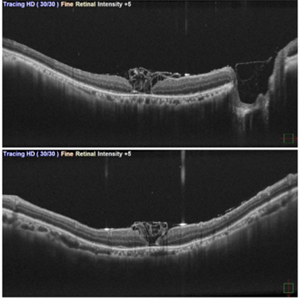

Inverted ILM Flap in RD with FTMH-First Post Op Day

Oct 29 2024 by SHILPI H NARNAWARE, ICO ( Retina) , FAICO ( Vitreo-Retina)

OCT showing stuffed ILM under oil on first post op day in a case of RRD with FTMH.

Photographer: Shilpi Narnaware, Sarakshi Netralaya , Nagpur, Maharashtra , India

Imaging device: Mirante ( by Nidek)

Condition/keywords: FTMH, Inverted ILM technique, RD